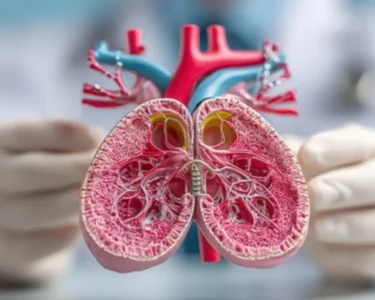

A new study published in the European Medical Journal sheds light on the significant impact of Childhood Interstitial Lung Disease (Childhood ILD) on the quality of life for affected children and their families. Childhood ILD is a group of lung disorders that cause scarring of the lungs, leading to breathing difficulties and various physical and emotional challenges.

Childhood ILD is a complex condition with various underlying causes, often unknown. The disease progresses differently in each child, ranging from mild to severe. Symptoms can include coughing, shortness of breath, fatigue, and chest pain, significantly affecting a child’s ability to participate in typical childhood activities.